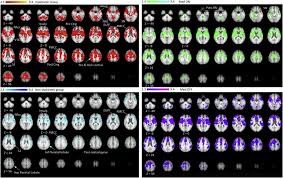

Pain And Dyskinesia In Parkinson S Disease May Share Common Pathophysiological Mechanisms An Fmri Study Journal Of The Neurological Sciences